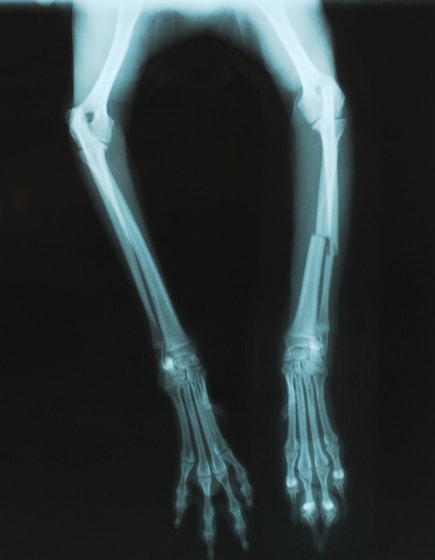

橈尺骨骨折 : 症例1 | 症例2 | 症例3 | 症例4 | 症例5 | 症例6 | 症例7

: 症例8 | 症例9 | 症例10 | 症例11 | 症例12 | 症例13 | 症例14

: 症例15 | 症例16 | 症例17 | 症例18 | 症例19 | 症例20 | 症例21